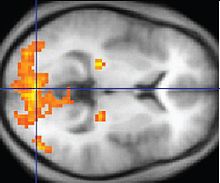

A Síndrome de Asperger é uma condição neuropsicológica que causa efeitos no desenvolvimento cerebral em geral, provocando mudanças nos vários sistemas funcionais existentes. Embora a dissociação da SA com outros transtornos do espectro autista ainda não seja clara e não tenha sido descoberta nenhuma patologia em comum para todos os distúrbios, há probabilidade de que a síndrome tenha mecanismos distintos das demais desordens. Alguns estudos neuroanatômicos e supostas ações de agentes teratogênicos presumem que a alteração no desenvolvimento cerebral ocorra logo após a fecundação. A migração anormal de células embrionárias durante o desenvolvimento fetal pode afetar a estrutura definitiva do cérebro e seus circuitos nervosos, afetando ligações diretamente relacionadas ao pensamento e comportamento. Existem várias teorias e estudos relacionados, porém nenhum fornece uma explicação completa a respeito do mecanismo da Asperger.

A teoria da underconnectivity trabalha com a hipótese do subfuncionamento das conexões e sincronizações neurais de alto nível e com um excesso de processos de baixo nível. Ela mapeia bem as teorias de processamento geral tais como a teoria da coerencia central fraca, que hipotetiza que uma capacidade limitada de ver grandes imagens adjascentes a disturbios centrais no TEA.